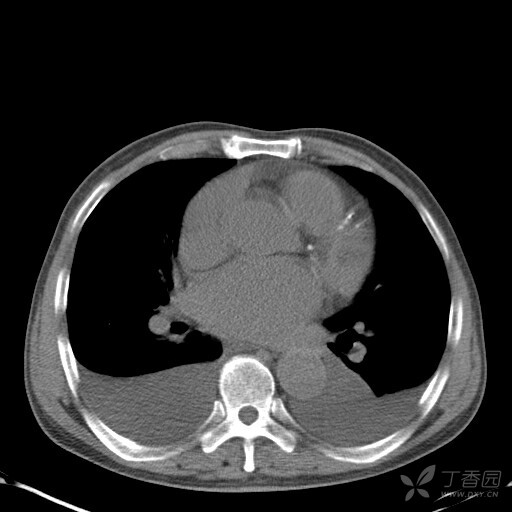

卧位胸片中胸腔积液的探讨 [精华]

图片尺寸 512x512